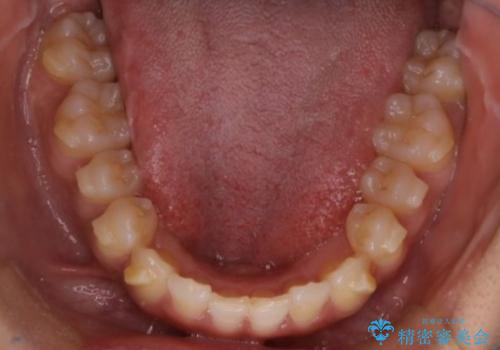

反対咬合と前歯のガタガタを非抜歯で改善

- 患者様は、上下の前歯のガタガタと反対咬合(下の歯が上の歯より前に出ている状態)を主訴として来院されました。診断の結果、抜歯を行わずに治療を進めるため、臼歯を遠心移動させてスペースを作り、IPR(インタープロキシマルリダクション)で歯間を調整する治療計画を立てました。インビザラインを使用して、透明で目立たない矯正装置により、歯列を整えながら噛み合わせも改善することを目標としました。

非抜歯での治療では、限られたスペースの中で効率的に歯を動かす必要があります。本症例では、臼歯を後方に移動させる遠心移動を行い、歯列のガタガタを改善しました。また、IPRを適切に行うことでスペースを確保し、歯根や歯肉への負担を最小限に抑えながら治療を進めました。インビザラインを使用することで、治療中も目立ちにくく、患者様の日常生活への影響を軽減しました。結果として、抜歯を行わずに美しい歯並びと自然な噛み合わせを実現し、患者様には大変満足していただけました。